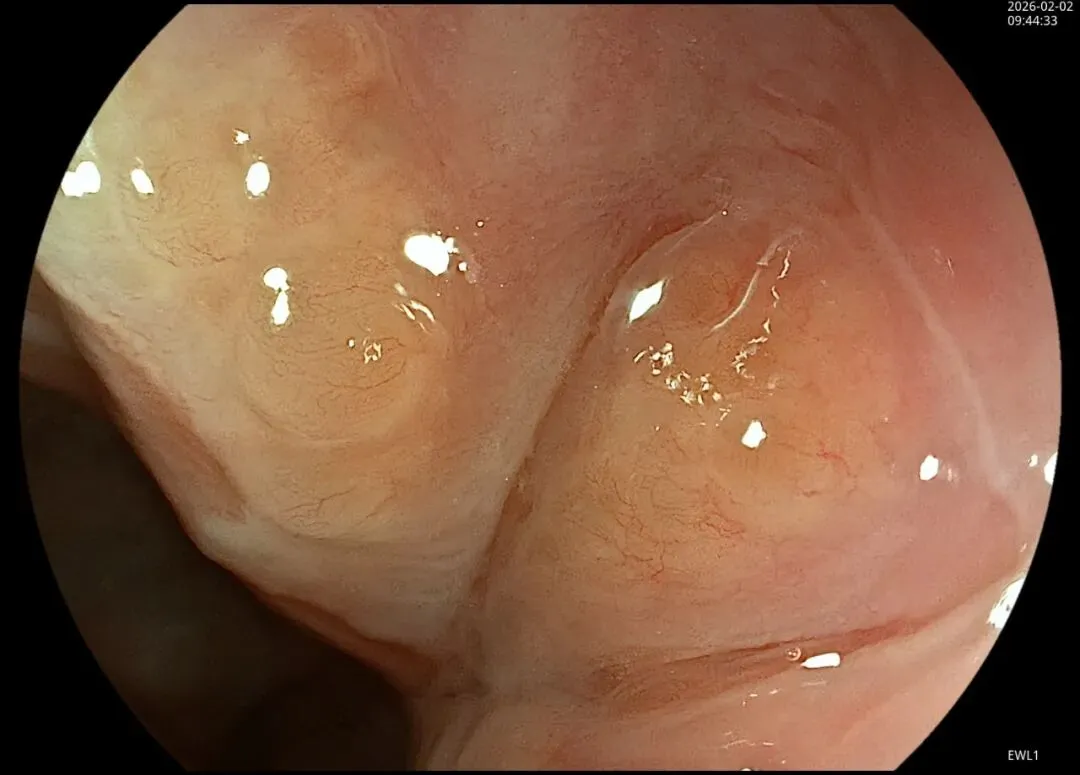

这一期不用码字,挺好的,很可惜一直没机会听过胡导讲的关于这个“花环征”的大课,学习内容来源于雨夜大师的号花环征:AIG背景的胃食管结合部的黄色颗粒状隆起及半透明“泡状”改变

补充自己在两例A型胃炎/AIG 观察到的“花环征”,巩固下学习效果。。。

case2:(made in china机子)👇

2.窄带光下可见颗粒状隆起呈褐色改变,放大可见细微网状血管结构及半透明“泡状”改变

进镜至贲门观察到“花环征”,提示存在AIG的可能,带学生的内镜老师这个moment可以装一把,不过。。。偶尔也有翻车的时候,以下这例是在“Hp现症感染C3萎缩”患者的花环